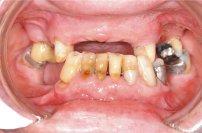

Ein 64 Jahre alter Patient wünscht eine Zahnsanierung (Abb. 1 und 2). Nach intensiver Abklärung des Zustandes der einzelnen Zähne der Restbezahnung sowie der Gesamtsituation (Abb. 3) und der Kostenzusammenstellung wurde folgende Therapie durchgeführt:

Ästhetisch wie auch funktionell entstand ein ausserordentlich schönes Resultat (Abb. 5 und 6).